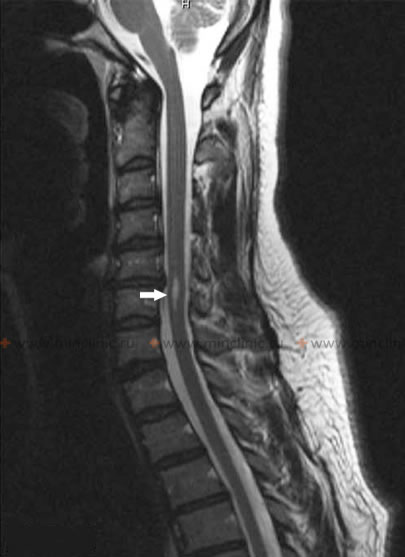

ზურგის ტვინის კისრის მაგნიტურ-რეზონანსულ ტომოგრაფიაზე ვლინდება სირინგომიელიის სივრცე C6 მალის სხეულის დონეზე (ნაჩვენებია ისრით).

ზურგის ტვინის კისრის მაგნიტურ-რეზონანსულ ტომოგრაფიაზე ჩანს სირინგომიელიის ორი, ლიკვორით ავსებული სივრცე (მითითებულია ისრებით).